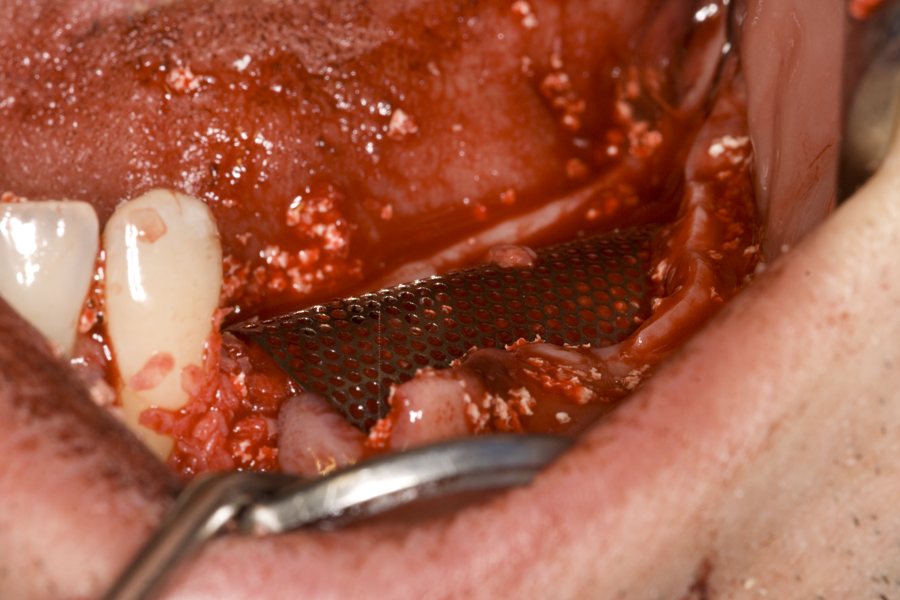

Около винтовете се поставя костозаместител, добре е да се размеси с

автогенна кост

Титанова мембрана